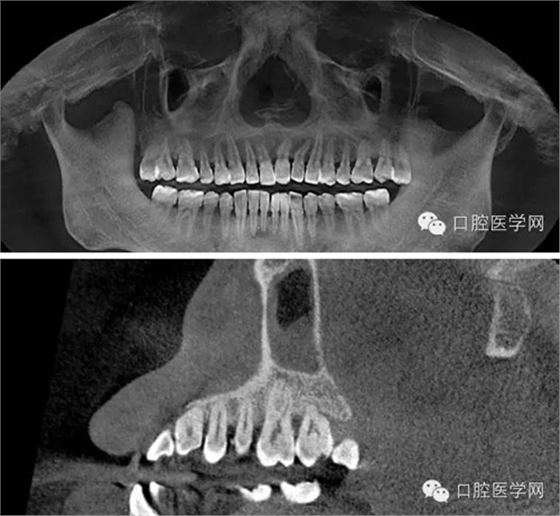

CBCT截圖:26根尖可見(jiàn)低密度透射暗影:

處置:必蘭局部麻醉后,于有出血點(diǎn)的牙齦乳頭處行縫合術(shù),縫合后出血明顯減少,組織同事會(huì)診,同樣口內(nèi)無(wú)明顯臨床表現(xiàn),拍攝CBCT,CT顯示26根尖可見(jiàn)低密度透射暗影,35、36、37無(wú)異常,為進(jìn)一步確診,遂與患者溝通采用麻醉排除法確認(rèn)患牙。26必蘭麻頰腭側(cè)浸潤(rùn)麻醉,待麻藥起效后,患者告知牙齒疼痛停止,觀察五分鐘無(wú)其他異常,遂確認(rèn)患牙,建議患者行根管治療術(shù)。交代治療過(guò)程,治療風(fēng)險(xiǎn),簽署治療同意書。